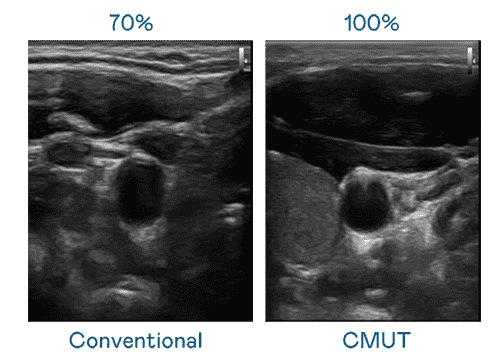

CMUT 技术是一种用电容式微机电元件来产生超音波讯号的技术。。。与传统 PZT 压电式技术相比,,CMUT 频宽增加 30%,,更宽频的超音波讯号让影像解析度大幅提升,,是实现高影像品质医疗超音波扫描、、、、促进精准医疗发展的关键技术。。。

大频宽带来超清晰影像

超音波影像的解析度高低,,,首先取决于探头能发出的讯号频宽。。。。JDB电子 CMUT 可提供高清晰的超音波讯号,,,提供高频宽、、、、高灵敏度、、影像纹理细节更高的超音波影像,,,,协助医护人员缩短影像判读时间及利用精准的医疗影像进行诊断。。。